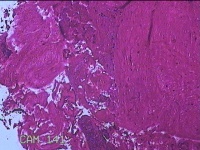

子宫腔内容物

性别

女

年龄

33岁

临床诊断

异常子宫出血;药流不全?宫腔占位

一般病史

阴道流血9天。

标本名称

大体所见

灰白暗红色不规则碎组织1.5x1x0.3cm一堆,未发现明显的绒毛样组织。